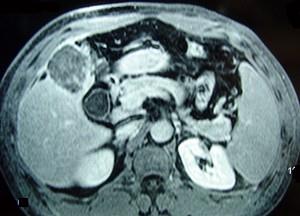

问题 男性,60岁,右上腹胀不适,右肝区叩击痛,影像检查如图,最可能的诊断是 ( )

选项 A.肝硬化 B.肝硬化、再生性肝癌 C.肝硬化、腹腔间质瘤 D.肝硬化、膈下脓肿 E.肝硬化、结节性增生

答案 B